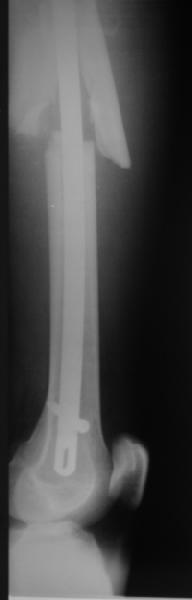

Мы бы не стали открывать, такие переломы срастаются, хотя бы и с

краевым дефектом. То есть если и удалять стержень потом, то сильно

попозже обычного. В приложении пример. Сразу после операции и через 11

мес. Понятное дело, пациент к тому времени давно и не хромал, и функция

колена была полная.